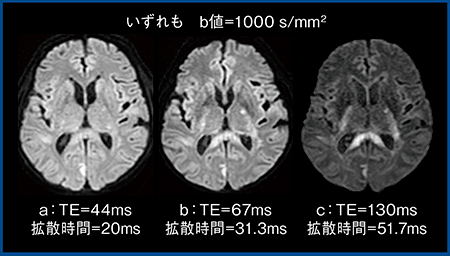

2.TEの影響

b値を1000s/mm2で固定したTEの異なる画像を比較すると,TEが短いほどSNRが高くT2 shine throughの影響も少ないため,DWIとしてはきれいである(図3)。しかし,コントラストはTEが短すぎる場合には低下しており,図3では,TE=67ms(b)の画像が最も病変を視認しやすい。これは,臨床機の場合,TEの変化に伴い拡散時間も変化するためである。また,TEや拡散時間の変化に伴いADCも容易に変化するため,ADCは絶対値ではないことを理解しておく必要がある。

図3 DWIにおけるTEの影響